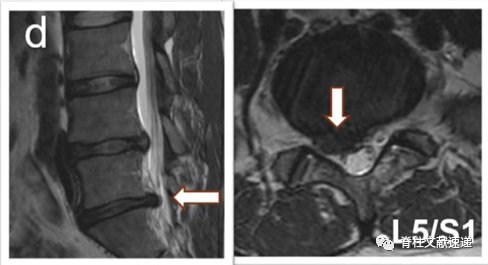

病例一:L5/S1椎间盘突出症,L4/5无症状椎间盘突出,行L5/S1固定融合术,3年后出现L4/5椎间盘突出症,行手术治疗,如下图,a为术前,b为术后。

病例二:L4/5椎间盘突出症,L5/S1无症状椎间盘突出,行L4/5髓核摘除术,术后3月,L5/S1椎间盘突出,行手术治疗,如下图,c为术前,d为术后。